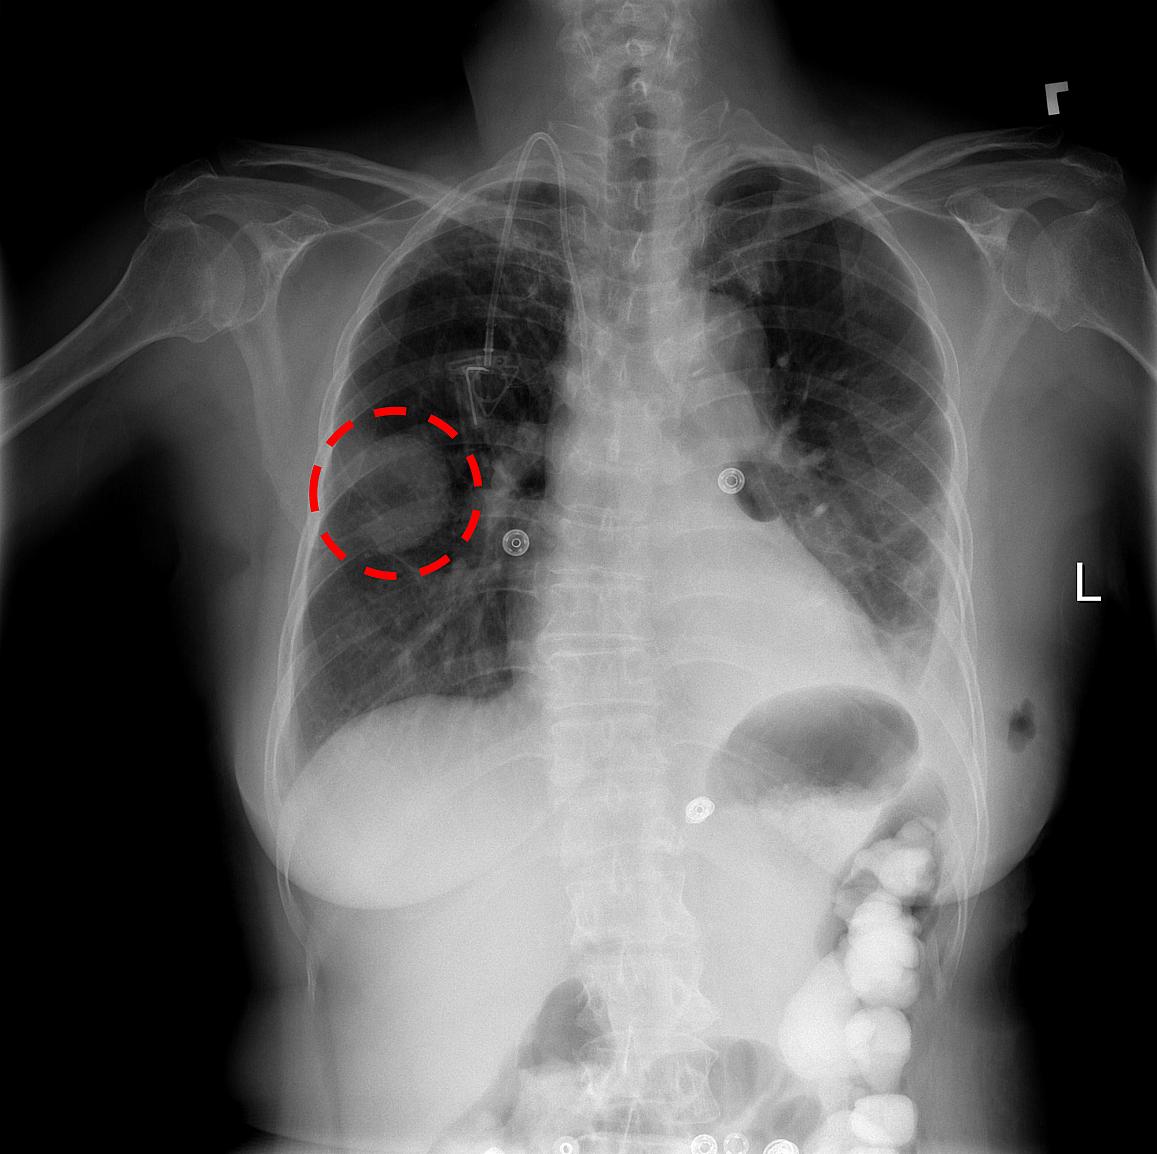

Covid19

Covid 19 Chest X Ray Images Dataset